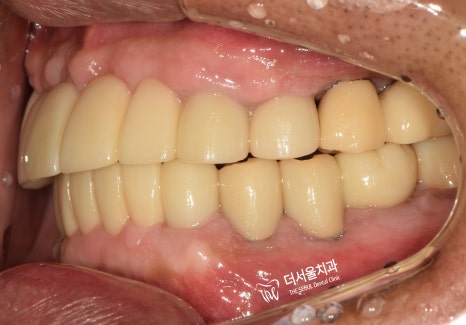

6. 최종 결과

완성된 보철을 전달받은 뒤,

그렇게 최종 보철을 세팅하며

꼼꼼하게 조정하고 마무리 지었는데요.

실제로 적용된 모습을 보면,

이전에 있던 진짜 치아랑 별반 다를게 없죠?

기능, 심미성 모두 신경써서

만들어드렸습니다.